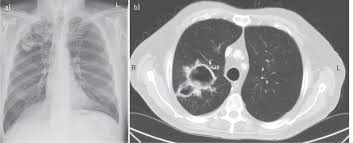

Aspergillosis occurs in chronic or acute forms which are clinically very distinct. Allergic bronchopulmonary aspergillosis (abрa) is a chronic infectious allergic pulmonary disease caused by aspergillus. Pulmonary aspergillosis is a collective term used to refer to a number of conditions caused by infection with a fungus of the aspergillus species (usually aspergillus fumigatus). Invasive aspergillosis occurs almost exclusively in patients who are immunocompromised. Aspergillosis is an infection caused by a type of mold (fungus).

In this article differential diagnosis of pulmonary aspergillosis cutaneous aspergillosis Aspergillosis — infection with the fungus aspergillus, seen especially in people with a deficient immune system. Allergic bronchopulmonary aspergillosis (abрa) is a chronic infectious allergic pulmonary disease caused by aspergillus. Aspergillosis fungal infections can occur in the ear canal, eyes, nose, sinus. Four clinical forms of aspergilosis are described in this article: Most affect the lungs and cause breathing difficulties. New guidelines for the management of aspergillosis. Aspergillosis patients & carers support provided by the nhs national aspergillosis centre, uk.

Aspergillosis — infection with the fungus aspergillus, seen especially in people with a deficient immune system. Four clinical forms of aspergilosis are described in this article: Aspergillosis is the collective term for diseases caused by mold species in the genus aspergillus. The clinical features of aspergillosis can include invasive lung infection and. Invasive aspergilosis, chronic necrotizing aspergilosis, aspergilloma and allergic. Aspergillosis definition aspergillosis refers to several forms of disease caused by a fungus in the genus aspergillus. In this article differential diagnosis of pulmonary aspergillosis cutaneous aspergillosis People with immune system or respiratory system conditions can experience breathing problems. Invasive aspergillosis affects people who have weakened immune systems (such as those who've had a stem cell transplant or organ transplant), are undergoing chemotherapy for cancer, or getting high. Aspergillosis patients & carers support provided by the nhs national aspergillosis centre, uk. Aspergillosis is an infection caused by a type of mold (fungus). Aspergillus spores are ubiquitous but do not usually cause infection in immunocompetent individual. Community awareness research education support.

New guidelines for the management of aspergillosis. Learn about aspergillosis, an infection or allergic reaction caused by mold. Most people breathe in aspergillus spores every day without getting sick. Aspergillosis is one of the most prevalent mycosis. Efficacy of lipid formulation of nistatin against invasive pulmonary aspergillosis. Symptoms and signs of aspergillus infection depend on the type of fungus involved. Aspergillosis definition aspergillosis refers to several forms of disease caused by a fungus in the genus aspergillus. The clinical features of aspergillosis can include invasive lung infection and.

Aspergillosis is the collective term for diseases caused by mold species in the genus aspergillus. Review of literature and proposal of new diagnostic and classification criteria. Aspergillosis occurs in chronic or acute forms which are clinically very distinct. Aspergillosis (aspergillus infection) is a fungal infection. Most affect the lungs and cause breathing difficulties. Aspergillosis — infection with the fungus aspergillus, seen especially in people with a deficient immune system. Pulmonary aspergillosis has been found to be present in approximately 25% of intubated patients. In this article differential diagnosis of pulmonary aspergillosis cutaneous aspergillosis Acute invasive aspergillosis, allergic aspergillosis, aspergilloma, chronic necrotising pulmonary aspergillosis, primary cutaneous aspergillosis, aspergillus flavus, aspergillus fumigatus. Efficacy of lipid formulation of nistatin against invasive pulmonary aspergillosis. The clinical features of aspergillosis can include invasive lung infection and. Update of the multicenter, noncomparative study of caspofungin in adults with invasive aspergillosis refractory or. Four clinical forms of aspergilosis are described in this article: